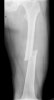

Cf) 대퇴부 골간골절(Femoral shaft fracture)

Femur의 전자 밑 부분부터 Supracondylar 사이의 골절입니다.

교통사고 같은 고에너지 외상이 주 원인입니다.

생명을 위협하는 폐, 복부, 머리 부위 손상이 동반된 경우가 흔합니다.

골절은 Femur의 AP, lateral view 검사로 진단이 됩니다.

대부분의 환자가 수술 적응증에 속합니다.

X-ray : 대퇴부 골간골절(Femoral shaft fracture)